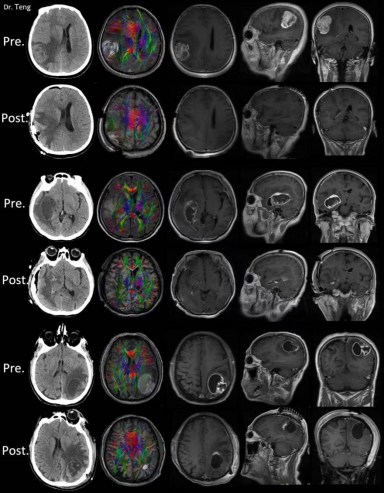

古稀之年的姜先生(化名),因“右侧肢体活动障碍伴记忆力下降加重15天”入院。CT筛查发现大脑内左侧顶叶功能区肿瘤。患者经多方询问,慕名找到滕雷求治,初步诊断为“左顶叶功能区肿瘤”。滕雷给与完善头部MRI及功能MRI检查,并详细评估肿瘤大小、位置、恶性程度及与神经功能纤维束的关系。系列检查显示患者大脑内左侧顶叶有一个直径达5cm的花环状肿瘤占位,功能磁共振结果提示肿瘤高度恶性,肿瘤组织已经严重推挤周围的运动功能区和神经纤维束,导致患者右侧肢体运动障碍。同时,患者出现昏睡的症状,意识状态变差,解除肿瘤的压迫已刻不容缓。

由于患者病情较重,肿瘤涉及脑功能区,单纯手术治疗极易导致患者出现偏瘫等神经功能缺失。滕雷团队在与家属充分沟通后,进行结合术中电生理监测、术中神经导航、术中超声辅助下的多模态开颅肿瘤切除手术。经过精准微侵袭显微手术技术和术中多模态技术结合的手术治疗,患者术后意识清醒,右侧肢体运动逐渐恢复并可下地行走,能够完成日常生活,记忆力和反应迟缓症状明显改善。